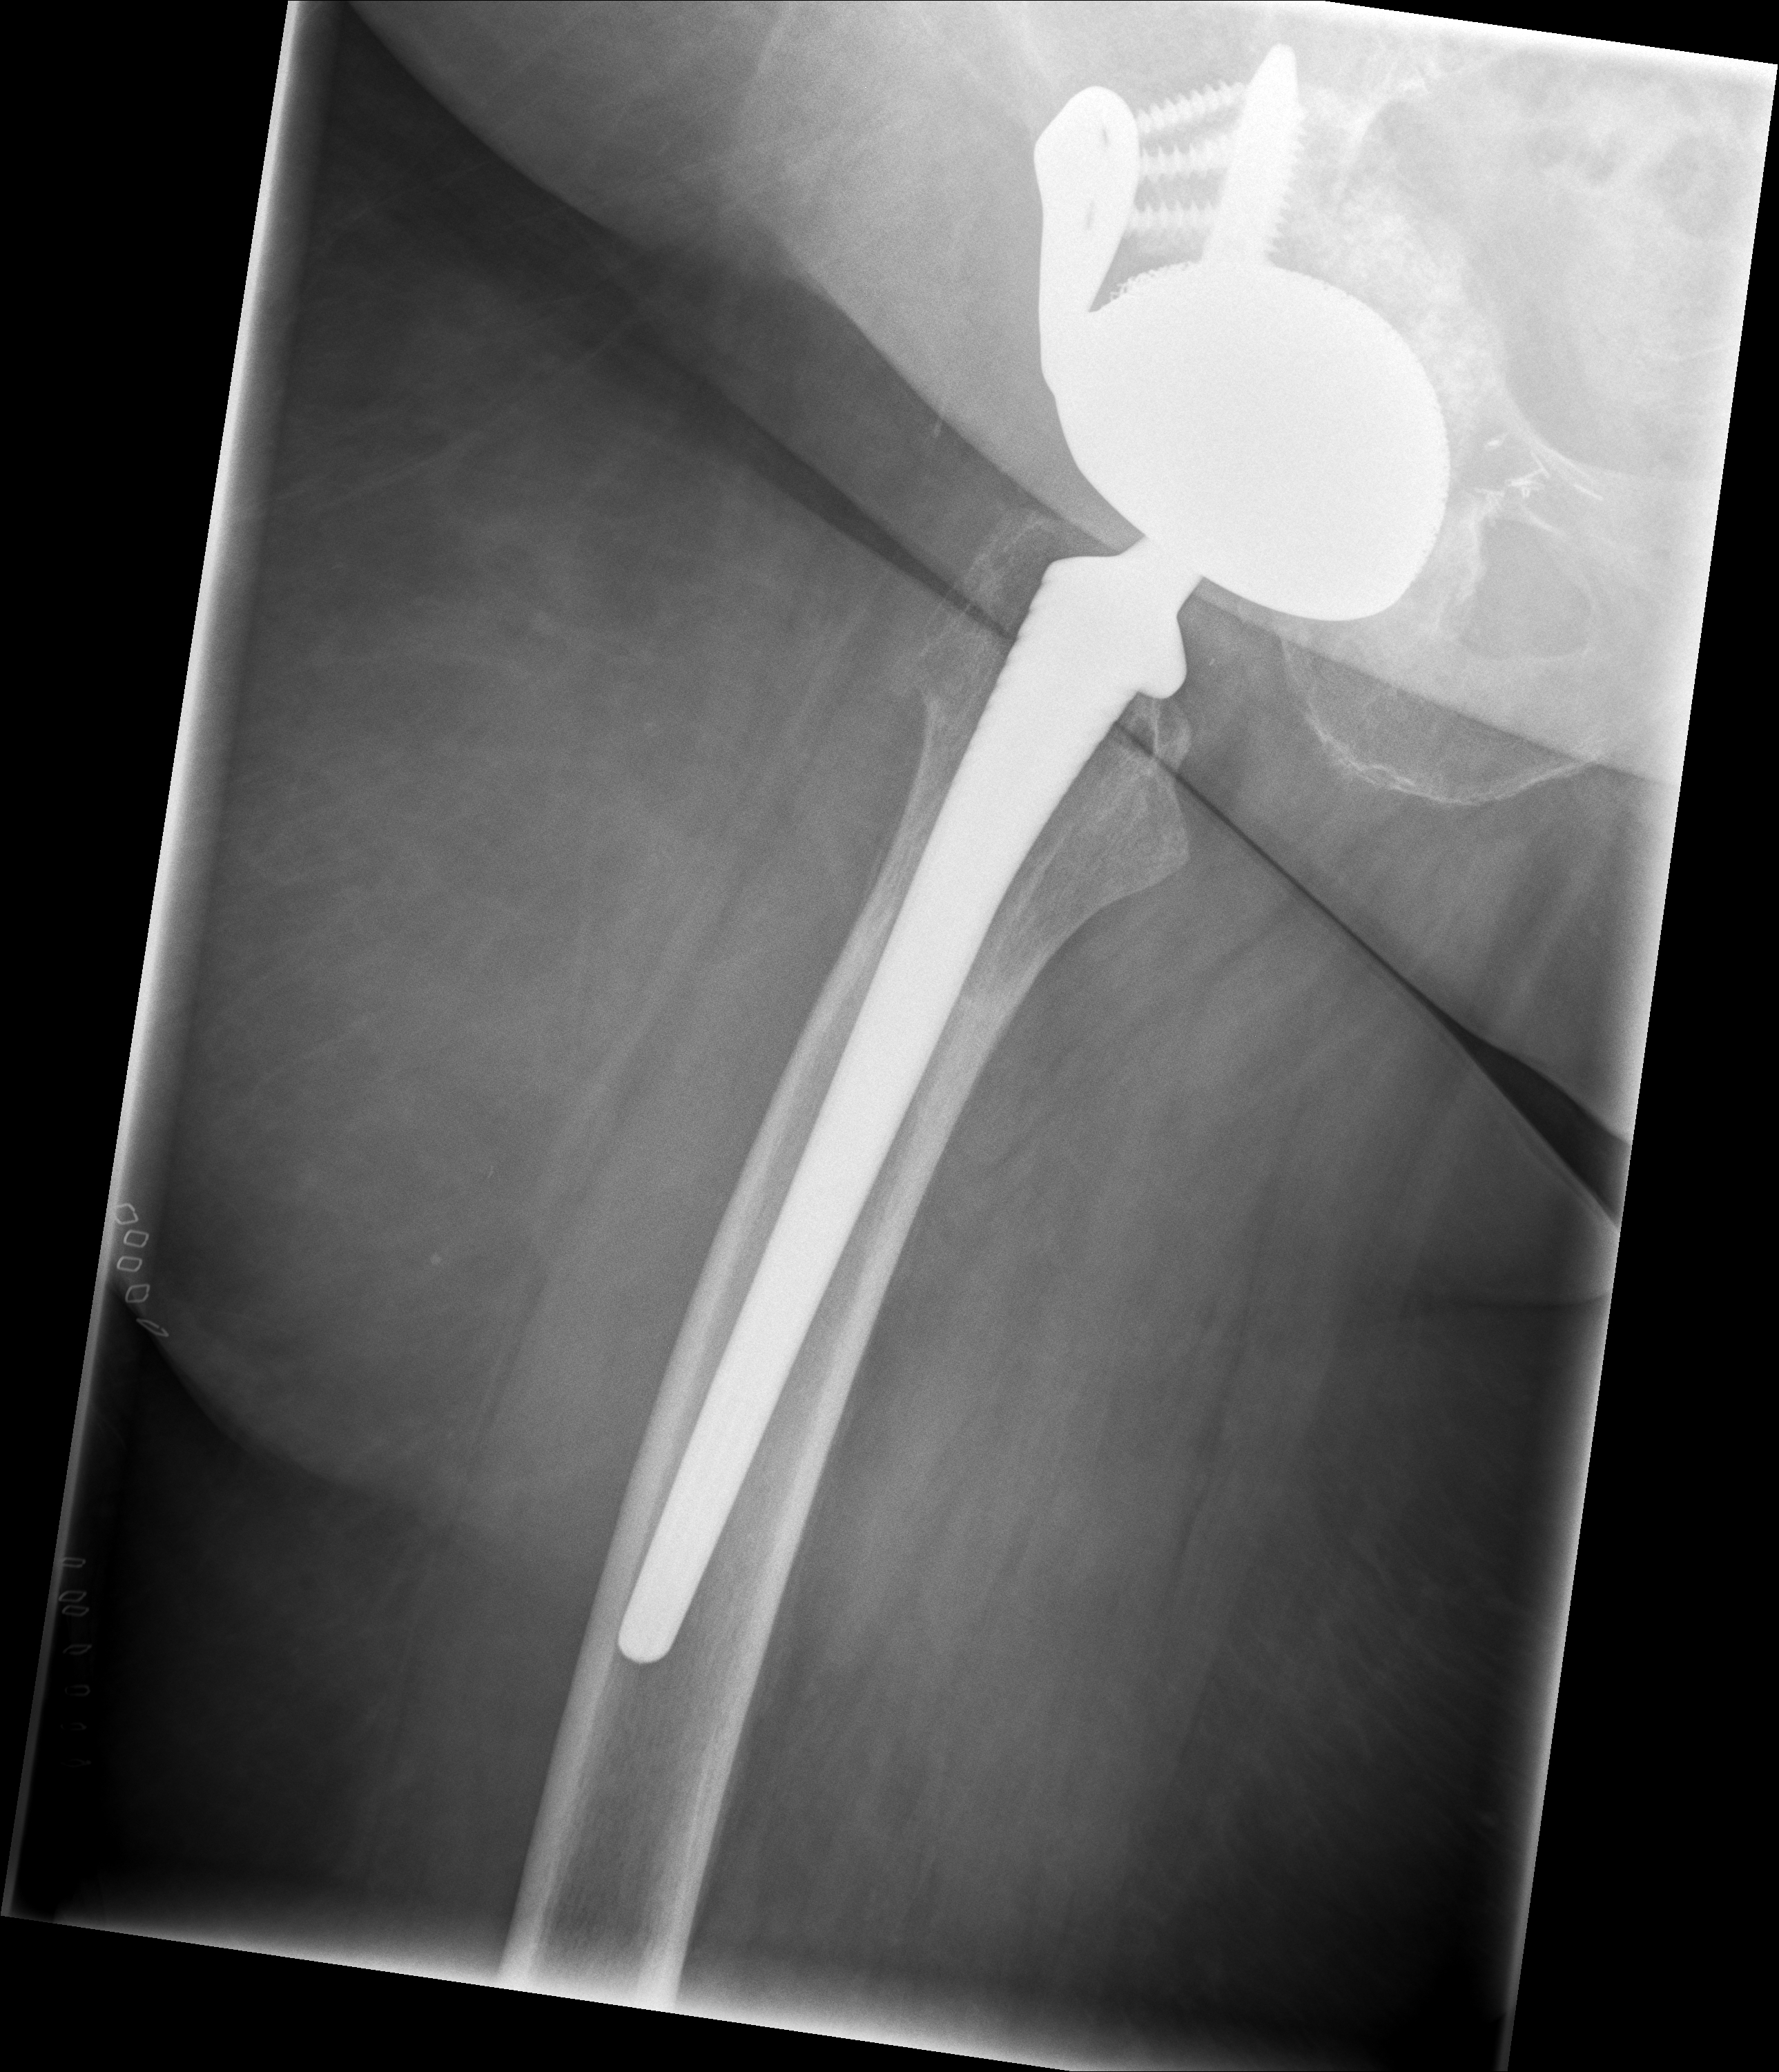

24.02.2026 - Neue TEP

Röntgen Februar 2026

Neue Hüft-TEP rechts nach Wiedereinbau

24.02.2026 - Neue TEP!

Becken 2026

Verlauf: Die Luxation/Pfannendislokation führte zur stationären Aufnahme im Universitätsklinikum Heidelberg (28.12.2025). Am 30.12.2025 wurde die TEP entfernt und ein Spacer implantiert. Infektnachweis: Enterococcus faecalis. Am 19.02.2026 wurde die neue Prothese erfolgreich eingebaut (stationär bis 05.03.2026). Komplikationsloser Verlauf, regelrechte Implantatlage im Röntgen. Entlassung mit 20kg Teillast, Amoxicillin für 6 Wochen. Wiedervorstellung am 09.04.2026.

24.02.2026 - Postoperativ

Röntgen Becken + Hüfte rechts (Kontrolle nach Wiedereinbau)

3 Aufnahmen | Becken tief + 2x Hüfte Lauenstein | 5 Tage nach OP

Postoperative Röntgenkontrolle

Röntgen Becken tief + 2x Hüfte Lauenstein R – Kontrolle 5 Tage nach Wiedereinbau.

Stationär 19.02.–05.03.2026. Zementfreie TEP (Fa. AQ Solutions Revisio M Pfanne + Fa. Depuy Synthes Corail Revision Schaft). Komplikationsloser Verlauf, reizfreie Wundheilung. 20kg Teillast. Amoxicillin 1g 3x tägl. für 6 Wochen. Wiedervorstellung 09.04.2026.

24.02.2026 - POSTOP

Röntgen Becken tief (nach Wiedereinbau)

DICOM

Kontrolle Becken 5 Tage nach Wiedereinbau TEP

Röntgen Hüfte Lauenstein R (1)

Kontrolle Hüfte 5 Tage nach Wiedereinbau TEP

Röntgen Hüfte Lauenstein R (2)